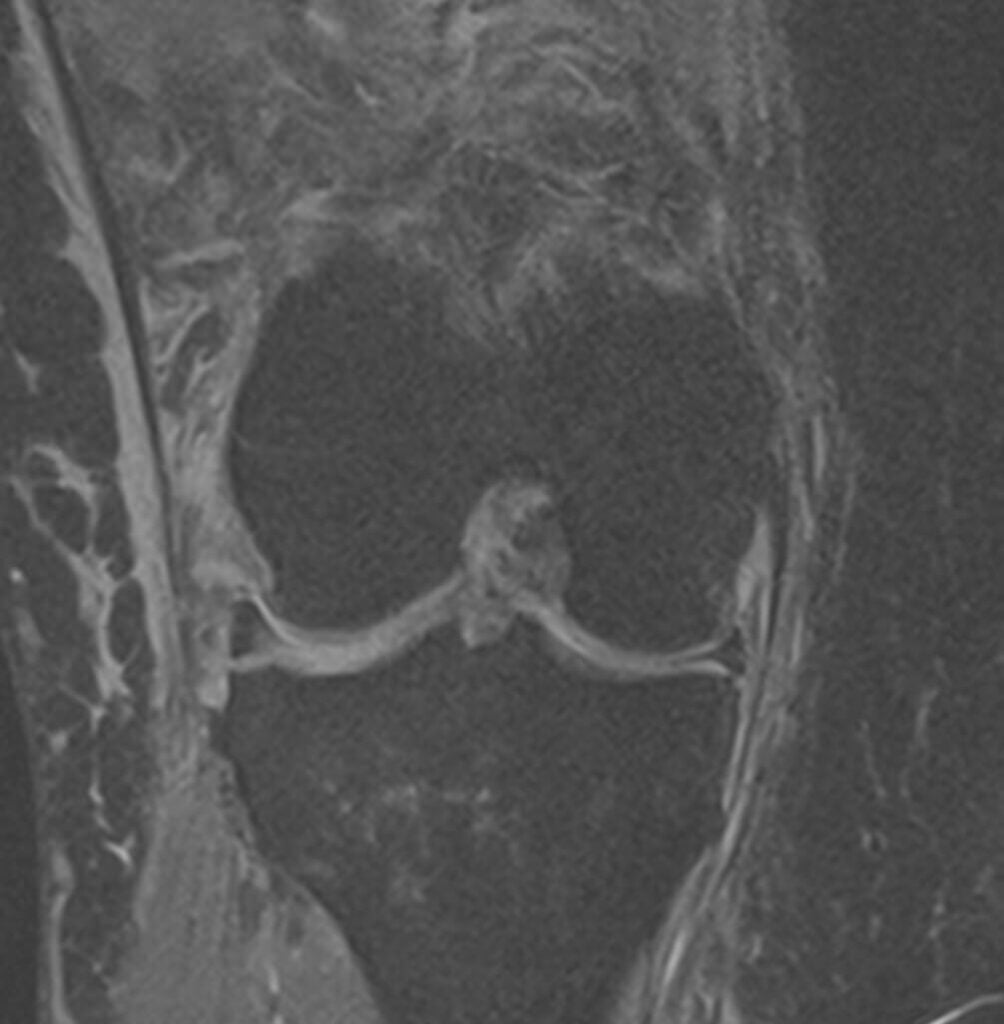

Ο ιατρός θα πάρει αναλυτικό ιστορικό και θα σας εξετάσει προσεκτικά. Μία ακτινογραφία θα αποκλείσει γρήγορα συνοδές κακώσεις των οστών (κατάγματα). Η διάγνωση επιβεβαιώνεται με μαγνητική τομογραφία (MRI), η οποία επιτρέπει την απεικόνιση συνοδών κακώσεων των μαλακών μορίων, όπως κακώσεις έσω πλαγίου συνδέσμου, ρήξεις έξω μηνίσκου ή οπίσθιας και έξω γωνίας. Σημειώνεται ότι η ρήξη μηνίσκου σε συνδυασμό με ρήξη χιαστού είναι εξαιρετικά συχνή.

– Μαγνητική τομογραφία